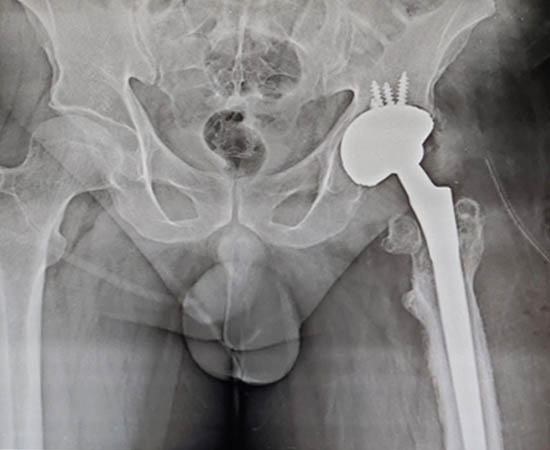

Pre Operation

Post Operation